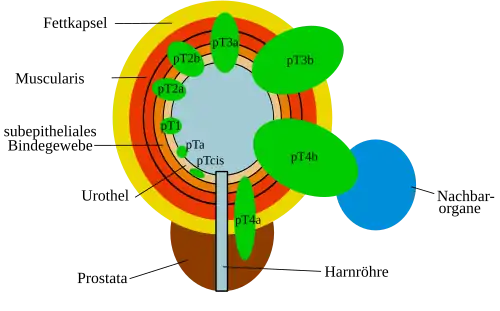

Die Einordnung von Schleimhauttumoren folgt nach der TNM-Klassifikation. Das Blasenkarzinom stellt hierbei keine Ausnahme dar. Die Klassifikation ist in der folgenden Tabelle grob umrissen:

| T | Ta | Nicht invasives papilläres Carcinoma in situ des Urothels |

| Tcis | Nicht invasives Carcinoma in situ | |

| T1 | Einwachsen unter die Schleimhaut in das submuköse Bindegewebe (Unterformen: T1a: oberhalb der Schleimhautmuskelschicht; T1b: unterhalb der Schleimhautmuskelschicht) | |

| T2 | Einwachsen in die Muskelschicht der Harnblase (Unterformen: T2a: innere Hälfte, T2b: bis in die äußere Hälfte) | |

| T3 | Hinauswachsen über die Muskelschicht der Harnblase (Unterformen: T3a: nur mikroskopisch erkennbar, T3b: mit dem bloßen Auge sichtbar) | |

| T4 | Einwachsen in Nachbarorgane (Unterformen: T4a: Prostata, Gebärmutter, Scheide, T4b: Becken- oder Bauchwand) | |